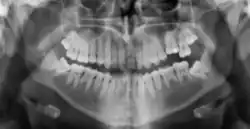

Radiographic appearance

On radiographs, enamel appears as the most radiopaque (white) structure due to its high mineral content.[19] Dentine and cementum are less radiopaque and are usually indistinguishable from each other.[19] The pulp chamber and root canals are radiolucent (dark), centrally located within the tooth structure. The periodontal ligament appears as a thin, radiolucent line between the root and the lamina dura.[19]